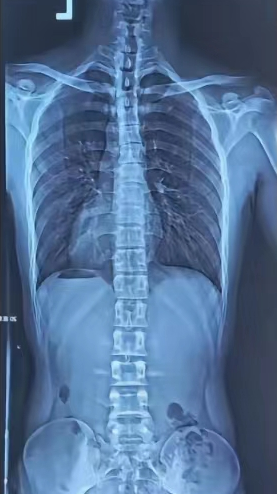

青少年脊柱侧弯是指脊柱在冠状位上偏离中线,出现弯曲或扭曲的现象。

正常脊柱示意图